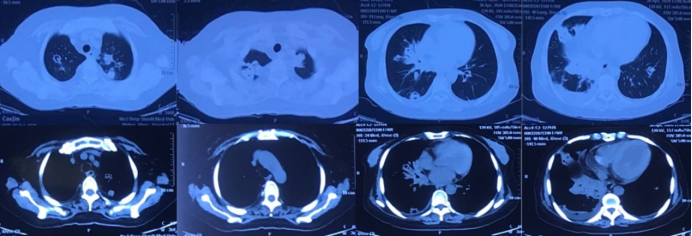

转入我科1周后,复查胸部CT示肺部病灶较前进一步进展(图3)。患者右小腿皮肤破溃范围扩大至4 cm×7 cm,周围红肿约6 cm×10 cm,肉芽组织不新鲜,有少许分泌物(图4)。此时痰、肺泡灌洗液(BALF)培养及mNGS结果回报均为鼻疽诺卡菌序列数44783)、金黄色葡萄球菌(序列数187,对TMP-SMX耐药,对美罗培南、利奈唑胺敏感。根据药敏结果换用美罗培南联合利奈唑胺继续抗感染治疗。右小腿皮肤破溃处请中医科会诊后给予中药化腐清创术、去腐生肌膏外用。

图3  患者转入我科1周后复查胸部CT